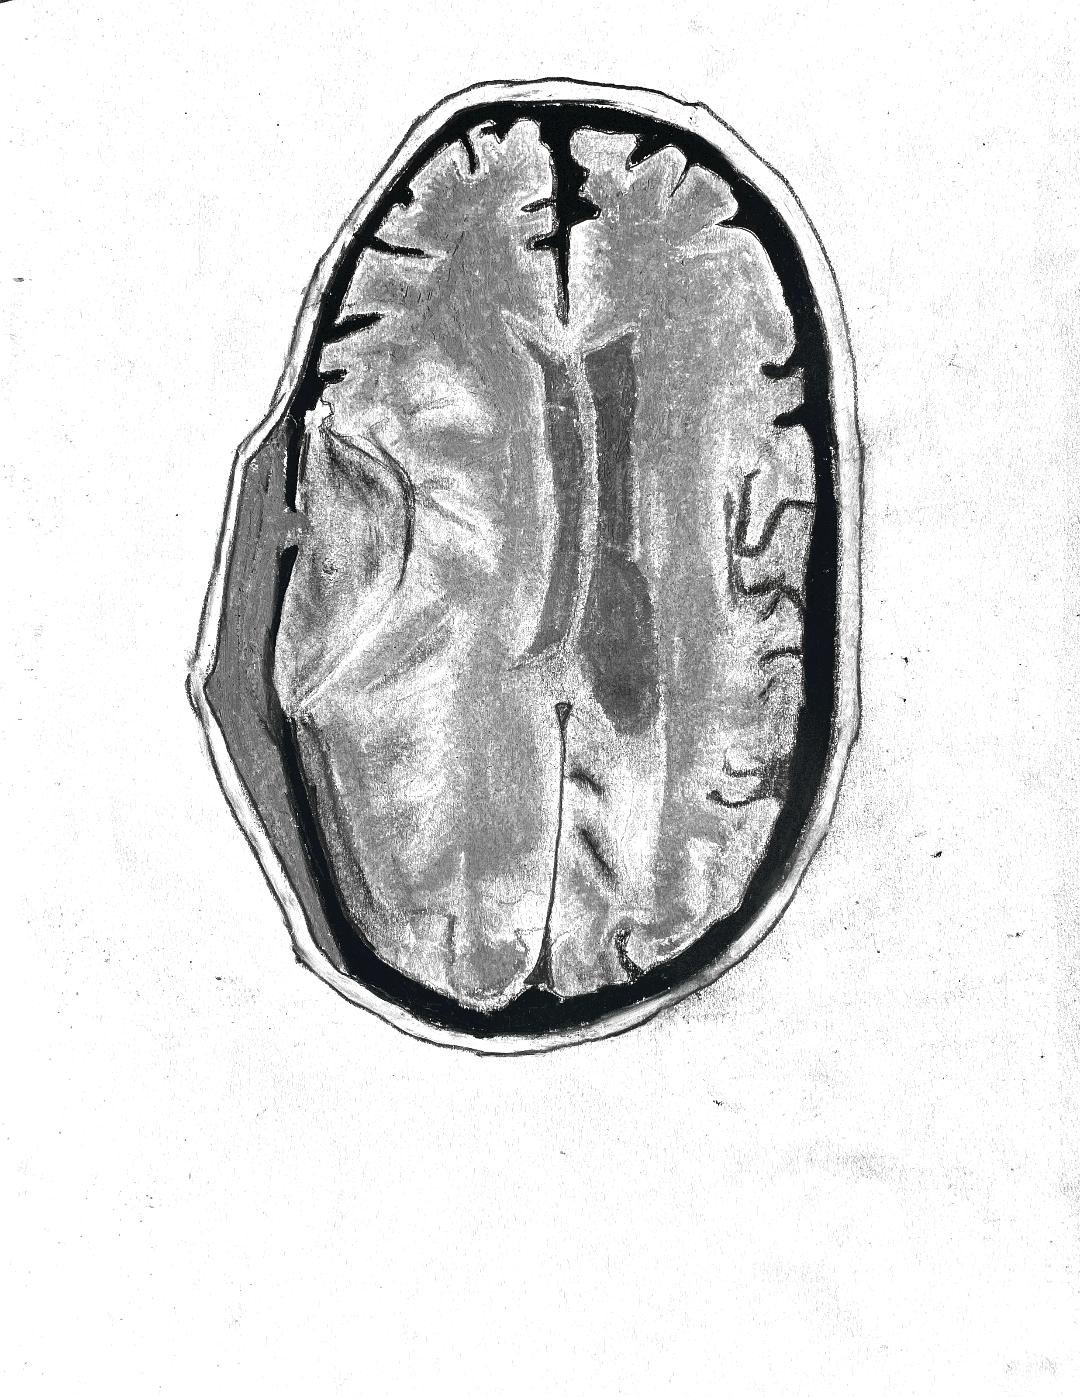

Acute on chronic subdural haematoma

Focal cortical dysplasia

Middle cerebral artery infarction

Middle cerebral artery (MCA) infarct